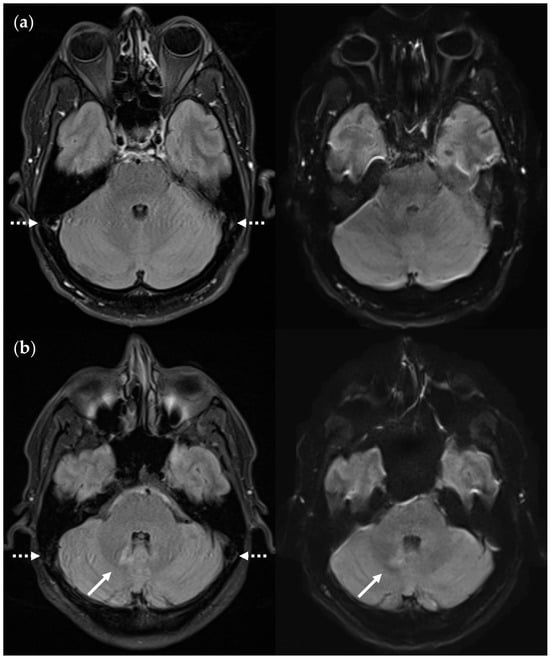

3.2.3. Dependence on Size and Location within FLAIRUF

3.3.3. Positional Dependence of SNR and CNR in FLAIRUF

4.3. Limitations of the FLAIRUF Images

4.4. Considerations on Ratings for Lesion Conspicuity in FLAIRUF

4.5. Outcomes Correlated with Technical Features